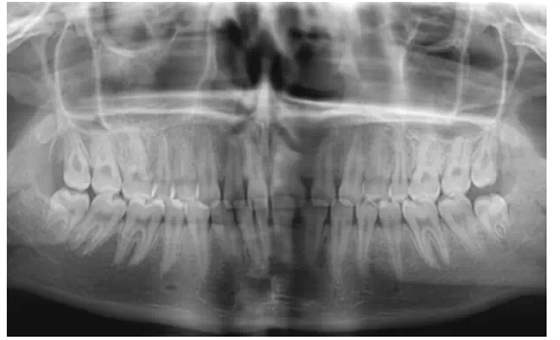

2、拍攝x線片

在修復(fù)前要判斷患者的牙周情況和牙齒的治療情況,做到知己知彼,為成功修復(fù)打下良好基礎(chǔ)。

曾有一個這樣深刻的教訓(xùn),患者因為前牙有縫,想做貼面修復(fù),剛做完的效果是很好的,可是過了半年,牙齒又出現(xiàn)了縫隙,通過x線片的檢查發(fā)現(xiàn),牙槽骨的吸收比較嚴重。所以,一定要對患者的牙周情況進行充分的把握。